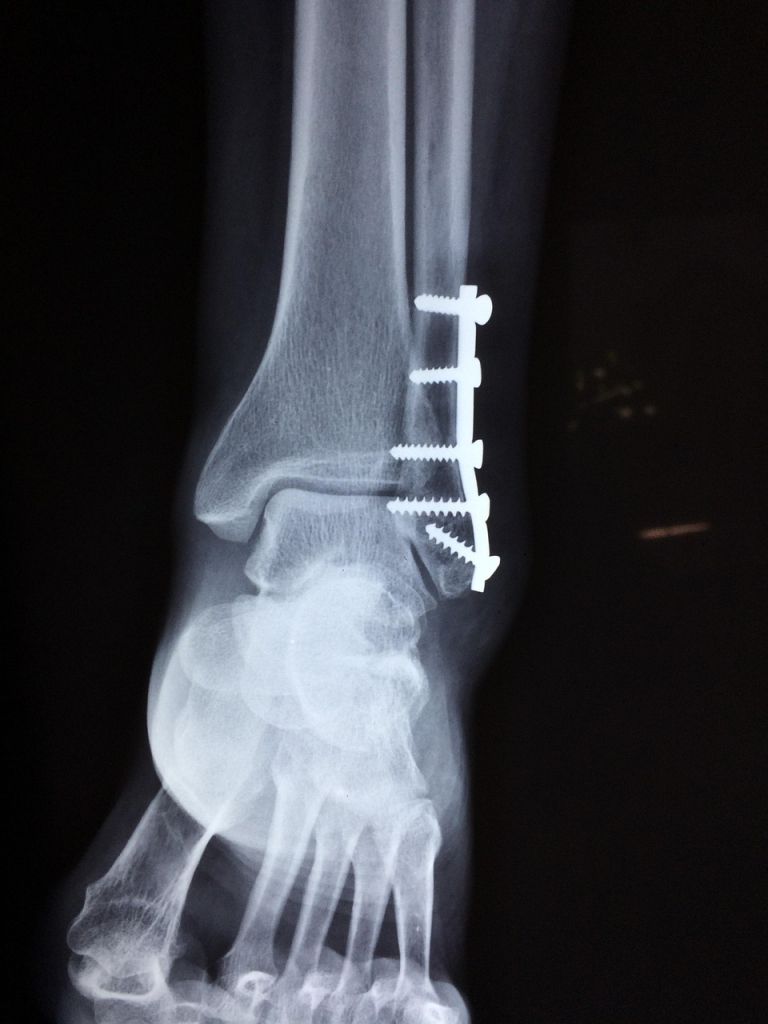

»Predvsem zaradi nadpovprečnega števila zlomov, ki so posledica padcev na spolzkih tleh. Urgentni center Celje še naprej vzdržuje višjo stopnjo pripravljenosti in okrepljene ekipe, vendar pozivamo vse, da pred obiskom urgentnega centra tehtno presodite nujnost obiska urgentnega centra,« pojasnjujejo v bolnišnici.